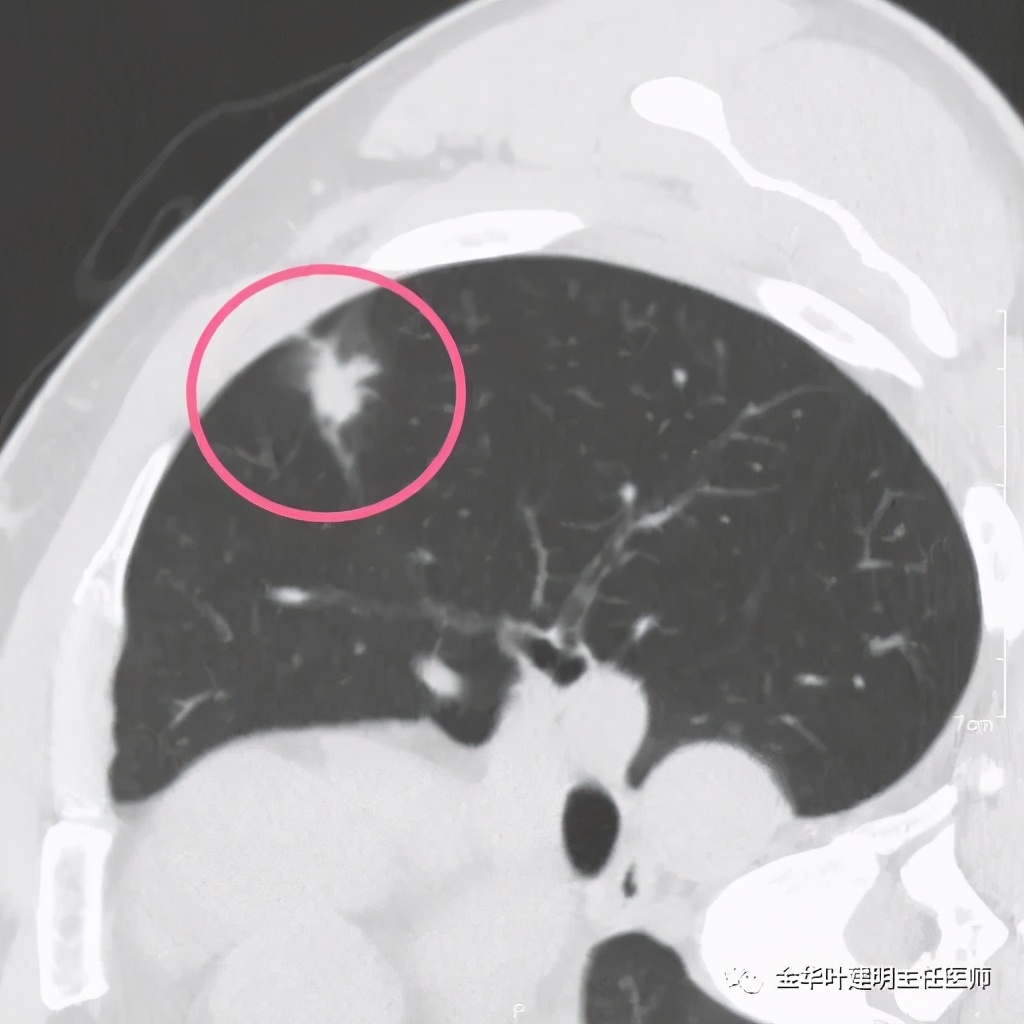

我们见左上实性病灶,主病灶旁有卫星灶,有血管进入,但也有贴边走行,边缘略显模糊,膨胀感与细毛刺不明显,收缩力也不明显。下面是其靶扫描的片子:

医生考虑炎性可能性大,予以头孢美唑抗炎治疗10来天,之后约一个月后复查了靶扫描,图像如下:

实性部分我看是有所缩小改善的,边上磨玻璃样的晕征更加明显了点

上图示病灶边缘向内凹陷,同时仍伴晕征